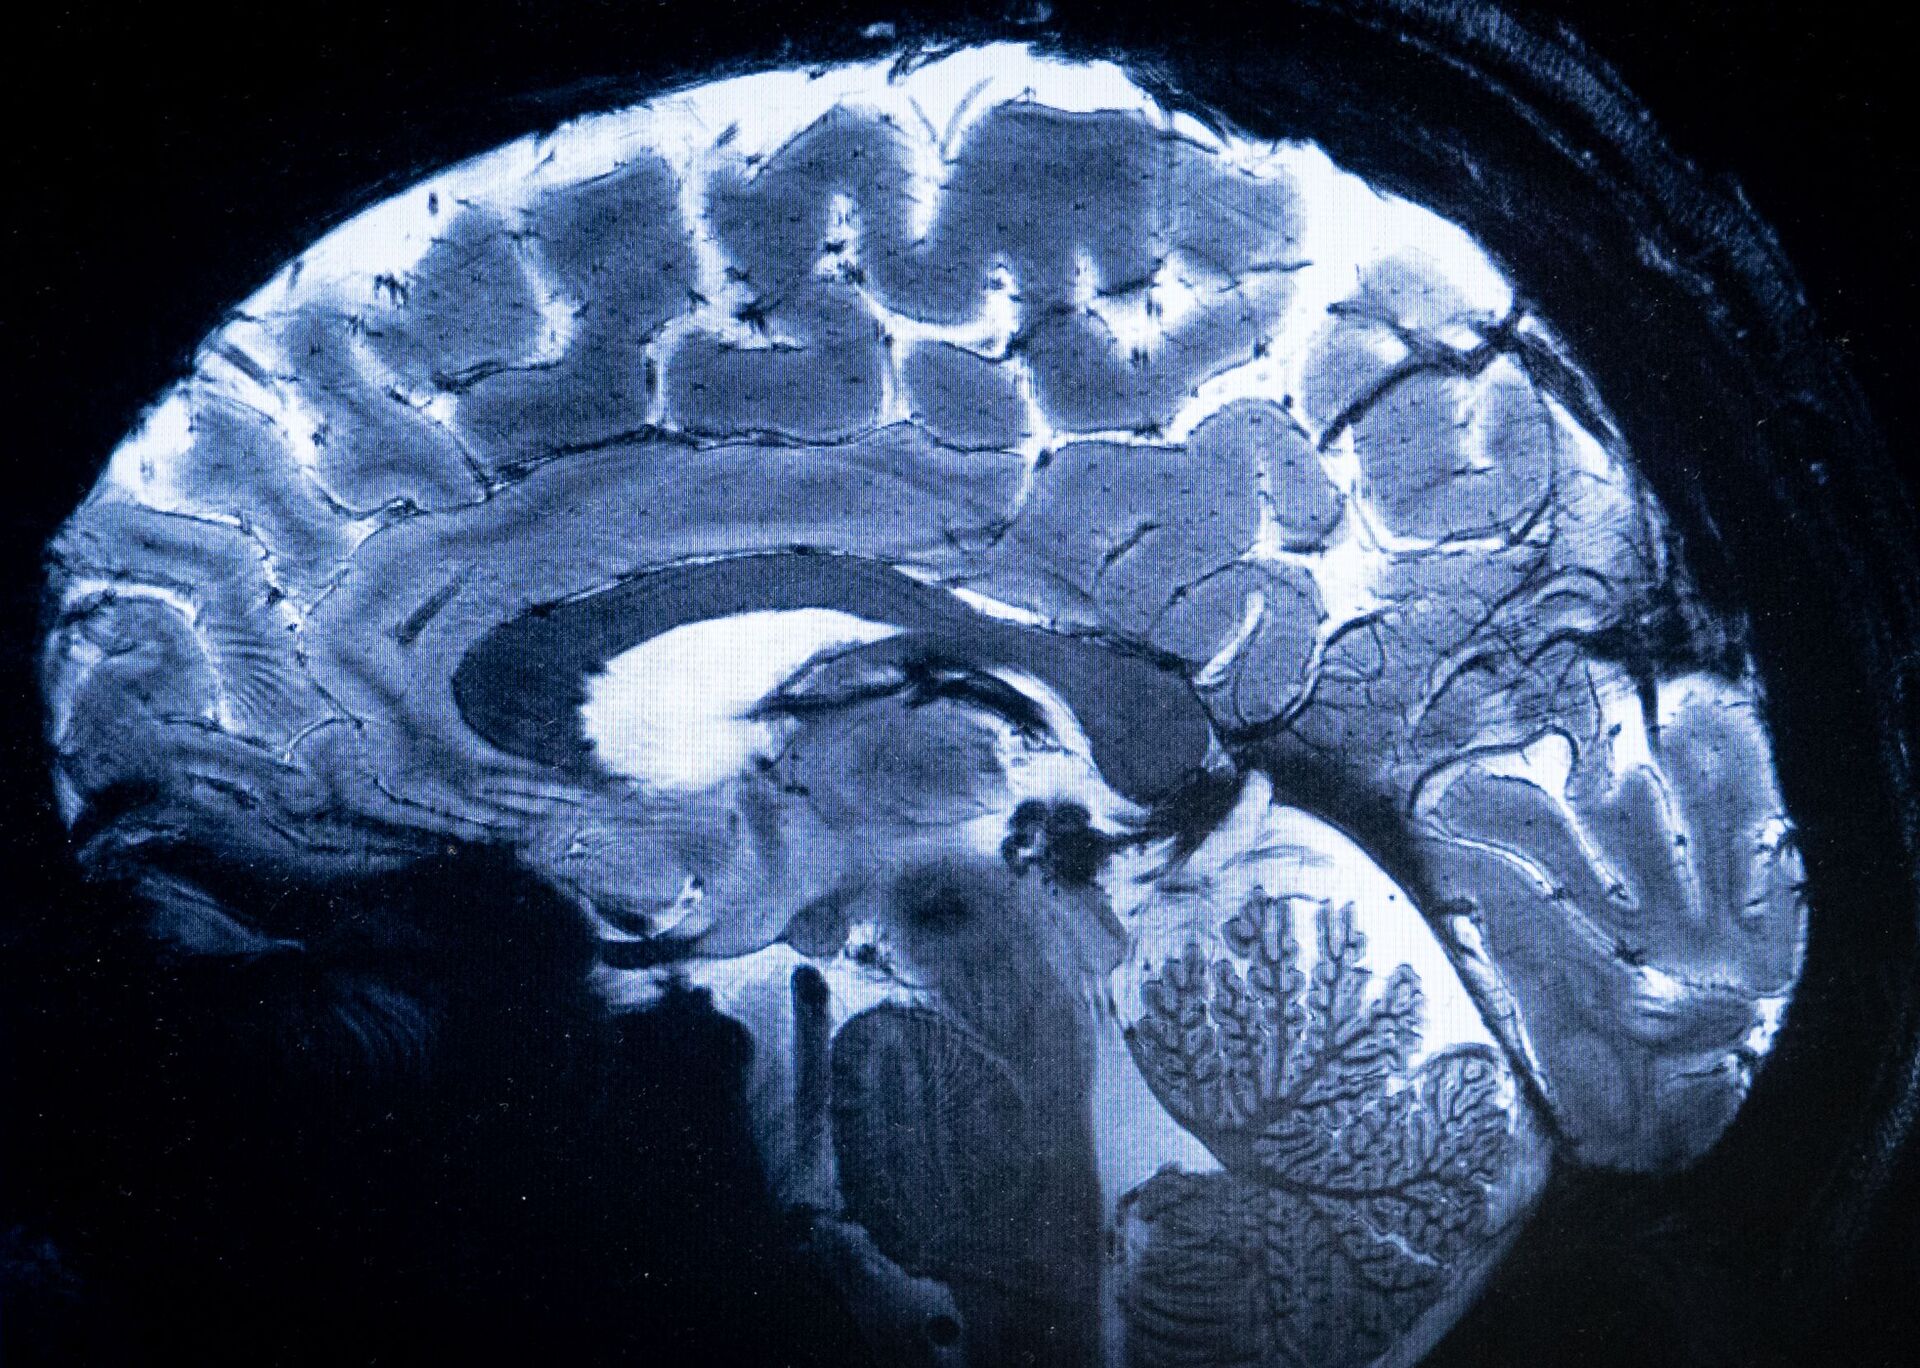

Hjernen er først færdigbagt i 30'erne

Hvornår er man voksen? Ny undersøgelse af hjerner viser, at det er senere end antaget